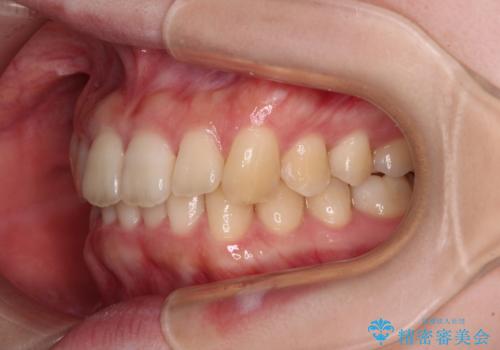

奥歯の咬み合わせを改善しながら、並行してインビザラインで歯列を整えることとしました。

カリエールディスタライザーやワイヤー矯正を併用したことで、確実かつ短期間で治療を終えることができました。